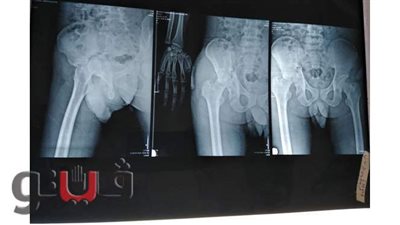

اعلن الدكتور سعد مكي وكيل وزارة الصحة بالدقهلية عن نجاح فريق طبي بإنهاء معاناة طفلة تبلغ من العمر 11 عاما كانت تعاني من إفراط مستمر في نشاط الغدد العرقية لليدين نتيجة وجود خلل في التحكم العصبي للعصب السمبثاوي المسئول عن افراز العرق اللازم لتنظيم درجة حرارة الجسم والذي أثر سلبا على ممارستها للحياة الطبيعيه اليومية .